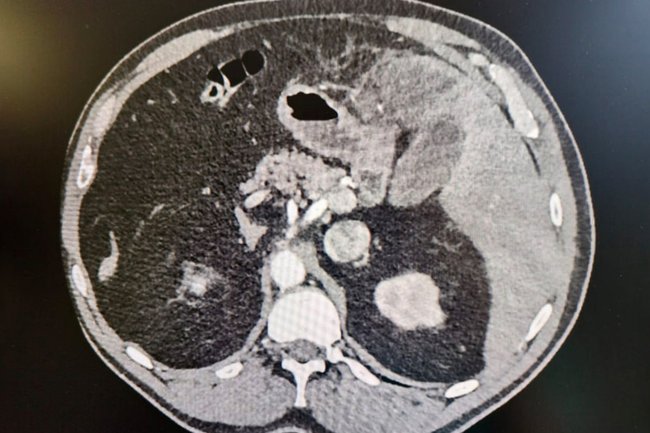

Диагностика показала, что рыбья кость пронзила кишечник и застряла в печени. Врачи приняли решение о проведении операции. Хирургическое вмешательство прошло удачно, и инородный предмет был успешно удален. Через три дня после операции мужчину выписали на дальнейшее амбулаторное лечение.